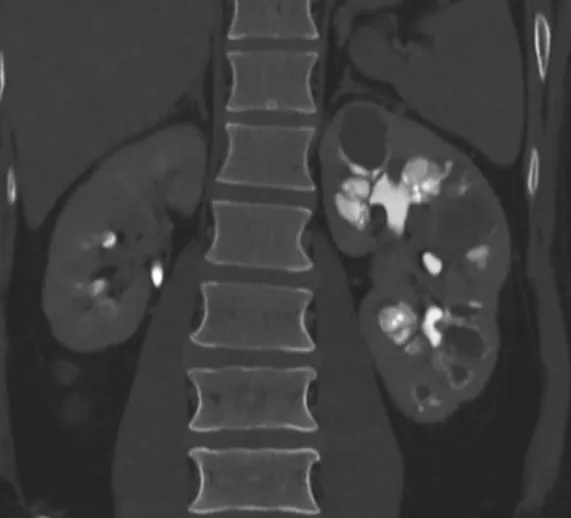

Uma causa incomum de hematúria glomerular intermitente!

Hematúria pós infecção, caso clínicos para auxiliar no entendimento de causas glomerulares comuns e raras...